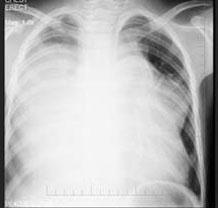

问题 男,13岁,胸痛胸闷2月,胸部检查如图,最可能的诊断为 ( )

选项 A、先天性心脏病,动脉导管未闭 B、右侧胸腔大量积液 C、纵隔占位 D、先天性心脏病,房缺 E、心力衰竭并右侧胸腔积液

答案 C